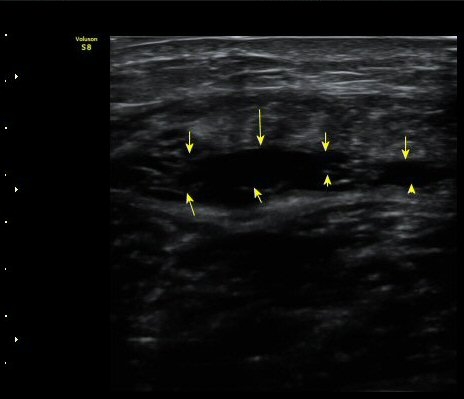

ÃÊÀ½ÆÄ °Ë»ç

¼ö»ó ÈÄ 2ÀÏ Â°

³»Ãø ºñº¹±Ù Á¾´Ü¸é°Ë»ç¿¡¼­ ±ÙÀ°°ú ÈûÁÙ ÀÌÇà ºÎÀ§¿¡ ÀÛÀº ÆÄ¿­°ú ¼ö¾× Àú·ù, ÆÄ¿­ µÈ

±ÙÀ°ÀÇ ±ÙÀ§ºÎ·Î ´ç°ÜÁüÀÌ °üÂû µÊ(±×¸² 1, 2, 3).